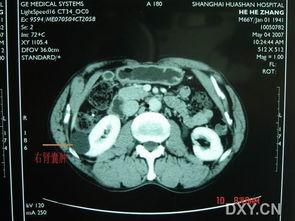

4. 观察囊肿:医生通过腹腔镜观察囊肿的位置、大小等,并确定手术方案。

5. 切除囊肿:医生会使用手术器械,将囊肿从肾脏中切除,并将囊肿内容物取出。